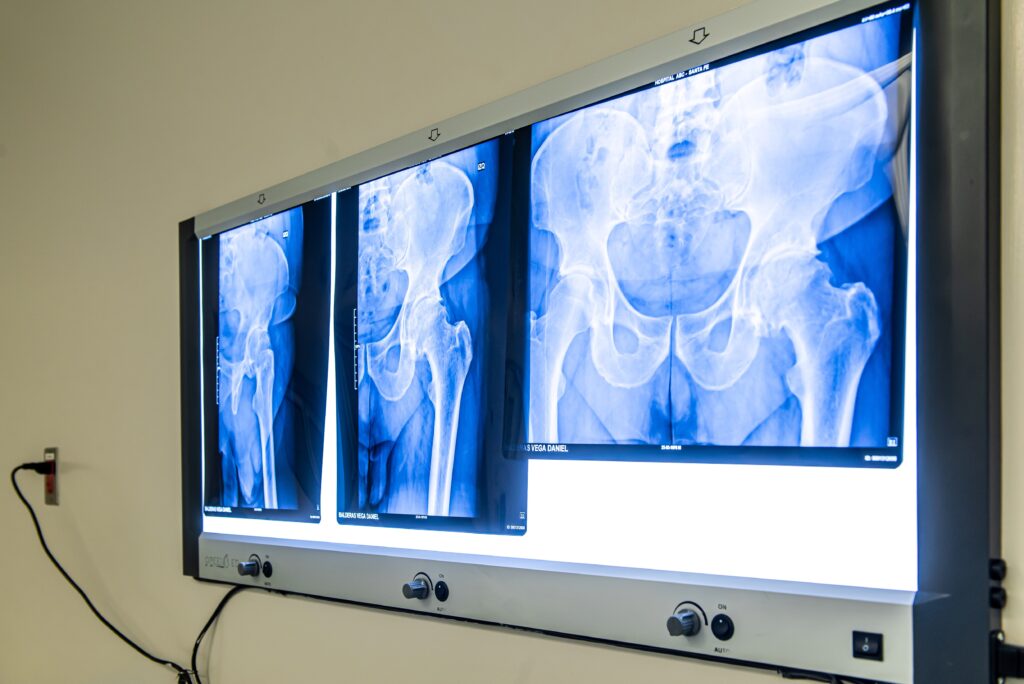

La detección de una lesión ósea se puede dividir en dos categorías:

• Lesión incidental. Esta se detecta cuando el paciente se realiza estudios por otra razón como una torcedura, y al momento de realizar la radiografía se descubre algo que hasta ese momento no molestaba a la persona y no se tiene conocimiento del tiempo de estar ahí.

• Lesión latente. Generalmente son lesiones que se ven, pero no duelen y se vigilan con radiografías para controlar su crecimiento, sin la necesidad inmediata de alguna intervención quirúrgica.